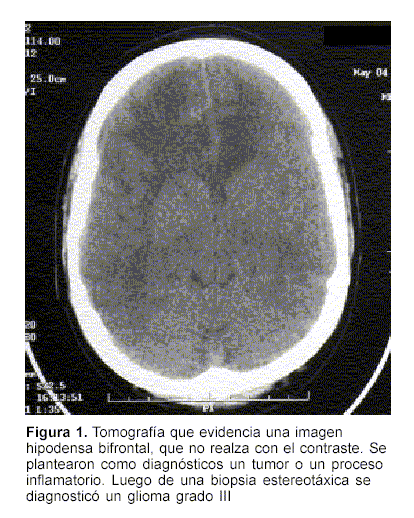

a) Tumores: en 11 casos se diagnosticaron gliomas de alto grado (III y IV). De estos pacientes, dos fueron operados posteriormente para resecar el tumor. En el primer caso se trataba de una lesión hipodensa frontal derecha. La imagenología planteaba la duda entre proceso inflamatorio o tumoral (figura 1). La biopsia determinó que se trataba de un glioma grado III. Luego de la resección quirúrgica fue sometido a radioterapia. Ha tenido una sobrevida de dos años sin secuelas invalidantes. En el segundo caso era una lesión parieto rolándica izquierda de unos 3 cm de diámetro. El diagnóstico fue también de glioma grado III. Se realizó una craneotomía y se resecó la lesión, la que se localizó siguiendo la diéresis cortical realizada para la biopsia. No agregó focalidad neurológica luego de la cirugía. Al momento de escribir este reporte está recibiendo tratamiento radiante. En los restantes casos los tumores eran de topografía gangliobasal o de cuerpo calloso (figura 2), y se consideraron fuera de las posibilidades terapéuticas. Se realizaron biopsias para descartar el diagnóstico de linfoma, tratable con quimioterapia.